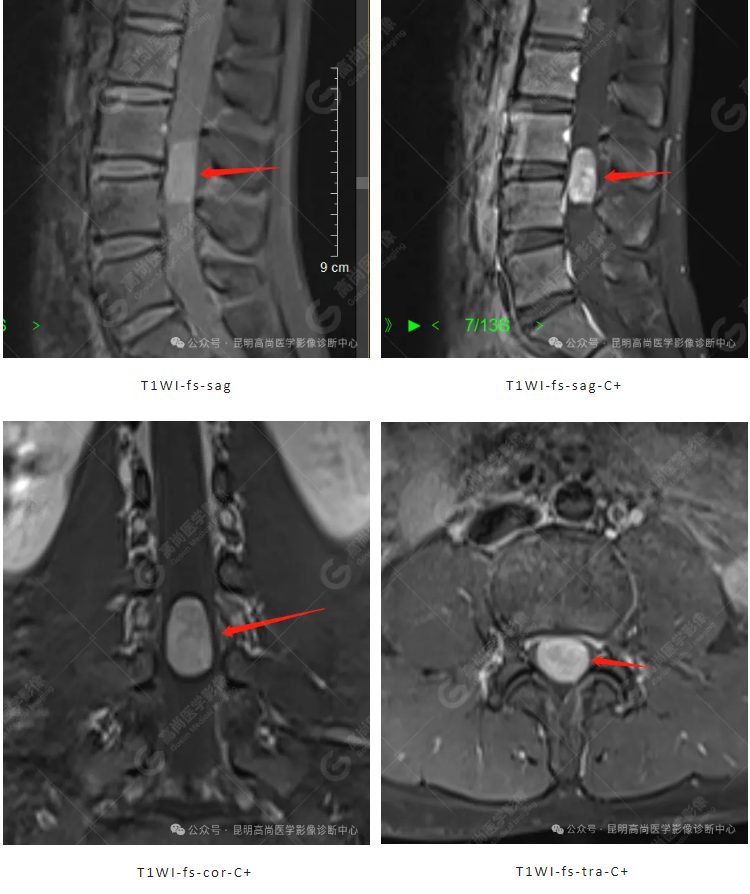

(椎管内肿物) 神经鞘瘤。

影像学检查中 MR 对病灶显示较好,呈类圆形、哑铃型,边界清,多位于椎管后外侧,T1WI 呈略低信号,T2WI 呈高信号,中心可囊变、偶见出血,增强后肿块明显强化,伴出血时不均匀强化,肿块从椎管内穿过椎间孔向椎管外生长,呈哑铃型,相应层面椎间孔扩张。